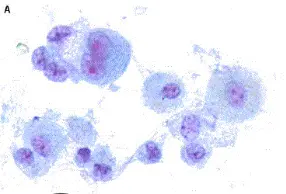

Acute Lymphoblastic Leukemia (ALL)

Scenario: 4-year-old boy with fever, hepatosplenomegaly

Abnormality in peripheral smear? Blast cells (lymphoblasts).

Diagnosis? Acute Lymphoblastic Leukemia (ALL).

Other Signs:

- Anemia signs: dizziness, pallor

- Thrombocytopenia: petechiae, purpura

- Recurrent infections

- Bone pain

- Weight loss

- Hepatosplenomegaly

Bone Marrow:

- Single cell blast

Confirmatory Investigations:

- Bone marrow aspiration and biopsy

- Immunohistochemistry

Treatment:

- Chemotherapy

- Supportive measures

Prognosis?

- Good prognosis if treated — children are cured in 90%

- Males treated for 3 years, females treated for 2 years

Findings: Leukemic morphology, cant diagnosis what type - however AURE ROD findings

would most likely point to AML